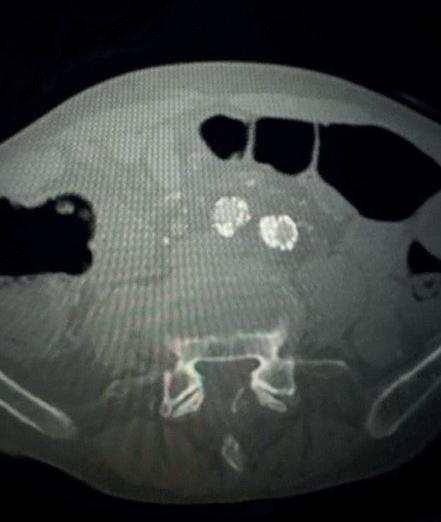

Case 2: The Shockwave M5+ tackles 90% stenosis of the distal SFA

The patient is a 75-year-old man with a history of hypertension, hyperlipidemia, CAD, chronic kidney disease and diabetes mellitus, who presents with a non-healing wound of the right lower extremity for three months. He had undergone diagnostic work—his ankle-brachial index (ABI) was found to be 0.73 with a toe pressure of 50mmhg, and a duplex ultrasound revealed a densely calcified superficial femoral artery (SFA) stenosis of 90%.

He was taken to the cath lab and underwent a right lower-extremity arteriogram. This confirmed a 90% stenosis of the distal SFA, with normal three-vessel run off. Due to the heavy calcium, we opted for a Shockwave M5+ 6x60mm and delivered 200 pulses to the lesion. There was no appreciable residual stenosis at the completion of the procedure, and his post-procedure ABI improved to 1.

This is a great example of how IVL can be used as a standalone therapy without the need for adjunctive treatment.

Figure 1. Pre-procedural angiogram

Figure 2. Pre-procedural angiogram

Figure 5. Final angiogram

Figure 2. IVL treatment angiogram

Figure 3. Post-IVL angiogram

Figure 6. Post-procedural CTA

Figure 3. Final angiogram